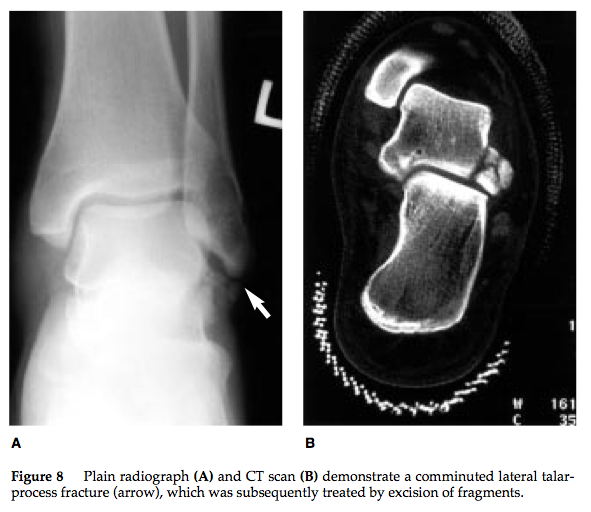

What is your approach to lateral process fractures